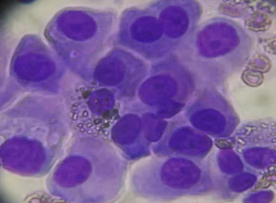

没想到我这么大岁数,切掉一个肺叶的十年后,再次做这么复杂的手术还这么顺利。 D大爷今年72岁,10年前曾行左肺上叶切除+淋巴结清扫术,手术标本病理为腺癌,术后给予了四次化疗。当时的胸部CT即可见右肺上叶小结节影,术后定期复查,病灶缓慢增大,一度略有缩小,此后再次逐渐增大。结合患者一直随访的影像学资料,杨如松院长考虑为右上肺新发恶性肿瘤。 2015年胸部CT 2020年胸部CT 虽然患者及其家属手术的意愿非常强烈,但此手术难度较高,原因在于: 1.患者年龄较高,手术风险大。 2.患者10 年前肺癌手术切除左边肺的一半,肺功能丧失较多。 3.病灶在右上肺的深部,切除有一定的难度。 为了保证患者术后的生活质量,我们不能够做肺的楔形切除这样的简单肺手术,而需要行肺段的切除。 EDDA重建提示病灶位置深 如果放在以前该患者就只能做做放化疗等保守治疗了。幸亏南京胸科医院目前引进了各种国内乃至国际上的先进技术。 如EDDA术前三D成像技术;只有单一3cm长切口的单孔胸腔镜技术;近红外荧光镜肺段、亚肺段精准定位技术等。 有了这些技术,杨如松院长心中有了底气。杨院长根据病人的情况设计手术方案,尽量减轻手术创伤,让接受第二次肺部复杂手术的高龄病人能够耐受,并且在术后能够顺利恢复。 根据术前EDDA三维重建,患者进行了单孔荧光胸腔镜S1a+2a切除术,术中先用ICG反染法确定段间面,再用膨胀萎陷法印证段间面,这保证了手术切除的精准性。 患者术中快速病理为贴壁型腺癌,这也印证了杨如松院长术前对患者肺结节良恶性的判断。 术后5天,D大爷非常顺利的出院了。出院前开心的窦大爷连声感谢杨如松院长:没想到我这么大岁数,切掉一个肺叶的十年后,再次做这么复杂的手术还这么顺利,谢谢、谢谢! 基本情况